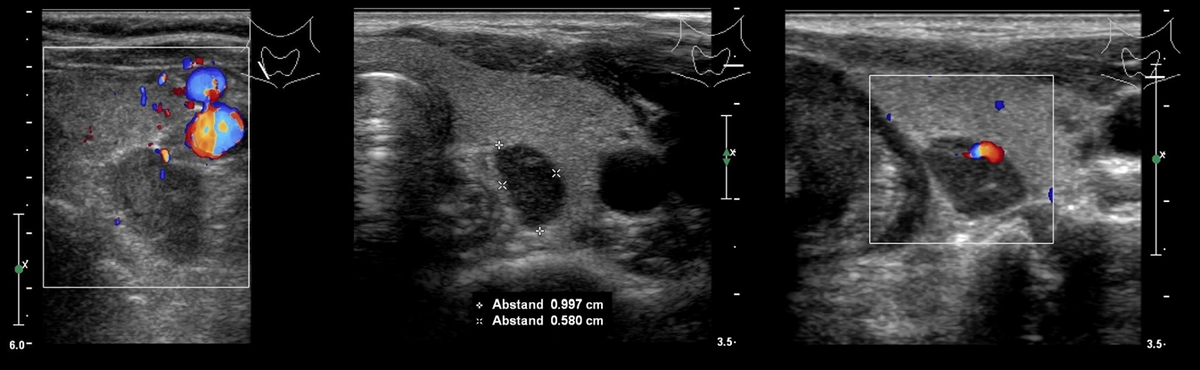

В режиме серой шкалы измененные ОЩЖ определяются в виде овальных, округлых или вытянутой формы гипоэхогенных образований чаще однородной структуры с ровными четкими контурами и размерами от 5-7 мм до 40 мм и более.

Важна оценка васкуляризации измененных ОЩЖ в режиме ЦДК/ЭДК: обычно их гиперваскуляризация ассоциируется с первичным или вторичным гиперпаратиреозом.

Выделяют 5 вариантов васкуляризации ОЩЖ по данным ЦДК (Mazzeo S. и соавт., 1997): I - отсутствие сигналов кровотока; II – очаговый кровоток в области сосудистого полюса на периферии железы; III - усиленный периферический кровоток; IV - усиленный центральный кровоток (паренхиматозный); V - усиленный центральный и периферический кровоток.

В спектральном допплеровском режиме систолическая скорость кровотока в измененных ОЩЖ составляет 15-50 см/с (в среднем 30 см/с).